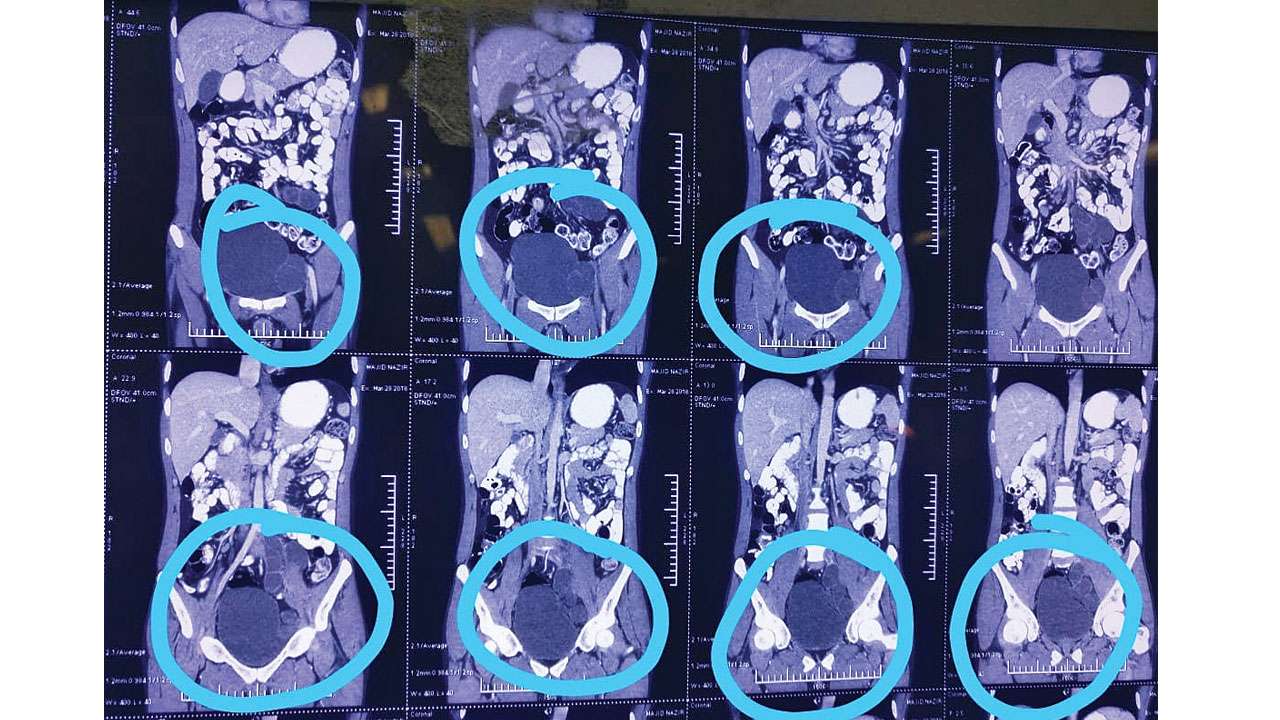

Ovarian cyst almost of a tennis ball size !! Cured !! Dr. Banerjee Cures Tennis Ball Size Cyst A baker’s cyst is a rounded swelling at the back of the knee. Just found out i have an ovarian cyst the size of a tennis ball. Danielle collins had a cyst the size of a tennis ball removed from her ovary recently. What is a vaginal cyst? Many things may cause a lump to appear in the groin or. Tennis Ball Size Cyst.

Doctors Removed a Tennis Ball Size Renal Cyst Through Robotic Surgery Tennis Ball Size Cyst Cysts may form due to injuries. I'm calling an obgyn on monday. I'm calling an obgyn on monday. A baker’s cyst is a rounded swelling at the back of the knee. Danielle collins had a cyst the size of a tennis ball removed from her ovary recently. And i’ve been more physically consistent in the. Vaginal cysts range in size. Tennis Ball Size Cyst.

Ovarian cyst almost of a tennis ball size !! Cured !! Dr. Banerjee Cures Tennis Ball Size Cyst But i’ve felt such relief since. A baker’s cyst is a rounded swelling at the back of the knee. Just found out i have an ovarian cyst the size of a tennis ball. And i’ve been more physically consistent in the. Can you give me some info/advice about ovarian cysts?:. Danielle collins had a cyst the size of a tennis. Tennis Ball Size Cyst.

Ovarian cyst almost of a tennis ball size !! Cured !! Dr. Banerjee Cures Tennis Ball Size Cyst Just found out i have an ovarian cyst the size of a tennis ball. And i’ve been more physically consistent in the. What is a vaginal cyst? Can you give me some info/advice about ovarian cysts?:. I'm calling an obgyn on monday. They removed a cyst the size of a tennis ball from my ovary, as well as material from. Tennis Ball Size Cyst.